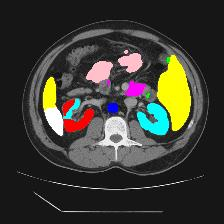

Medical image segmentation is one of the most fundamental tasks concerning medical information analysis. Various solutions have been proposed so far, including many deep learning-based techniques, such as U-Net, FC-DenseNet, etc. However, high-precision medical image segmentation remains a highly challenging task due to the existence of inherent magnification and distortion in medical images as well as the presence of lesions with similar density to normal tissues. In this paper, we propose TFCNs (Transformers for Fully Convolutional denseNets) to tackle the problem by introducing ResLinear-Transformer (RL-Transformer) and Convolutional Linear Attention Block (CLAB) to FC-DenseNet. TFCNs is not only able to utilize more latent information from the CT images for feature extraction, but also can capture and disseminate semantic features and filter non-semantic features more effectively through the CLAB module. Our experimental results show that TFCNs can achieve state-of-the-art performance with dice scores of 83.72\% on the Synapse dataset. In addition, we evaluate the robustness of TFCNs for lesion area effects on the COVID-19 public datasets. The Python code will be made publicly available on https://github.com/HUANGLIZI/TFCNs.